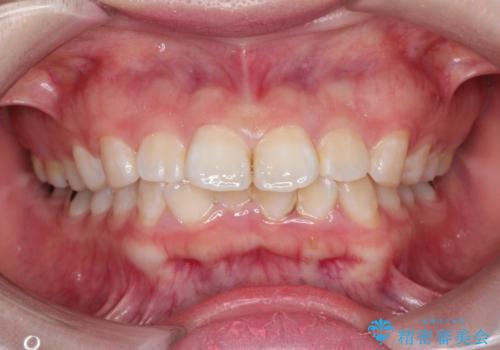

- 20代女性

- 2年6ヶ月

- 口元が出ていることを主訴に来院されました。

上下左右小臼歯を抜歯して審美装置で治療を行いました。

口元もスッキリと変化し、大変満足していただきました。